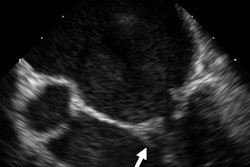

The team used an ultrasound scanner with vector flow imaging to image the hearts of two three-month-old babies, one with a healthy heart and one with congenital heart disease. The technology allowed for complete transthoracic imaging of tissue and blood flow at a depth of 6.5 cm; abnormal flow and cardiac anomalies were clearly visualized in the child with congenital heart disease.

Vector flow imaging demonstrates swirl of blood flow within the dilated main pulmonary artery of a pig. Image courtesy of Dr. Morten Jensen, PhD."Vector flow imaging technology is not yet possible in adults, but we have demonstrated that it is feasible in pediatric patients," Jensen said in a statement released by the university April 3. "Our group demonstrated that this commercially available technology can be used as a bedside imaging method, providing advanced detail of blood flow patterns within cardiac chambers, across valves, and in the great arteries."